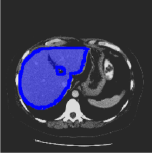

Consider a three-dimensional object within a volume. It is straightforward to produce a 3D bounding box of the object by finding its extreme points in the three coordinate axes. While this 3D bounding box will be tight in the 3D sense, its rectangular cross-sections will not, in general, remain tight with respect to the planar cross-sections of the volume. Fig. 1 illustrates such a case for the task of liver segmentation in a CT volume. In the Experiments section we show that the success of existing 2D weakly-supervised segmentation methods relies on the bounding boxes being tight and therefore the tightness of the individual 2D bounding boxes should be corrected before training and applying a segmentation CNN.

(a)

(b)

(c)

(d)

The global bounding box tightness prior mentioned above assumes that each of side of the box is sufficiently close to the target region. This means that for any region shape, each vertical or horizontal line inside the bounding box will cross at least one pixel belonging to the target region. This condition does not hold when the provided annotation comes as a 3D bounding box which is represented as a series of per-slice non-tight 2D bounding boxes. In this case, there will exist vertical or horizontal lines shown as stripes in Fig. 1 (d), that will lie outside of the actual object boundary. In the Experiments section we demonstrate the poor performance of the weakly-supervised approach from [5] when the user-provided bounding box is much wider than the true object of interest.